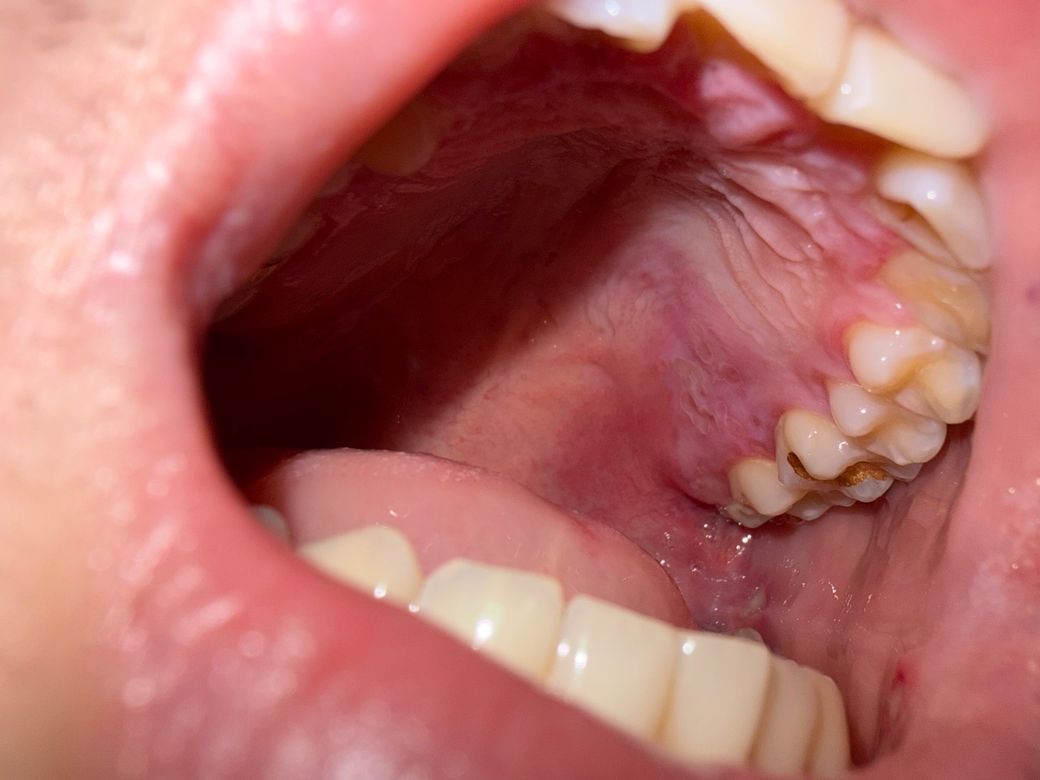

왼쪽이 어제 저녁 두번째 사진이 오늘 아침

• 2번 째 사진

올려주신 사진에서 목 젖 주변이 첫 번째 사진 외 잘 찍히지 않아 호전 여부의 평가가 어렵습니다.

목젖 부위가 2, 3번 사진에서는 나와 있지는 않으니 전반적으로 호전되었는지 알기는 다소 어렵습니다. 오른쪽 아래 1개 있는 것은 변화를 볼 수 있는데, 큰 호전은 없는 것 같아요. 가장 중요한 것은 증상의 호전입니다. 안 아프면 좋아지고 있는 것이라고 볼 수 있지요.

사진 비교상 급격한 진행이나 궤양 확대, 화농성 변화는 뚜렷하지 않아 명확한 악화로 보이지는 않습니다. 현재 통증 강도가 비슷하고 발열이 없다면 급성 세균성 편도염 가능성은 낮아 보이며, 이미 항생제를 복용 중이라면 추가적인 항생제 증량이나 변경이 즉시 필요한 상황으로는 보이지 않습니다.